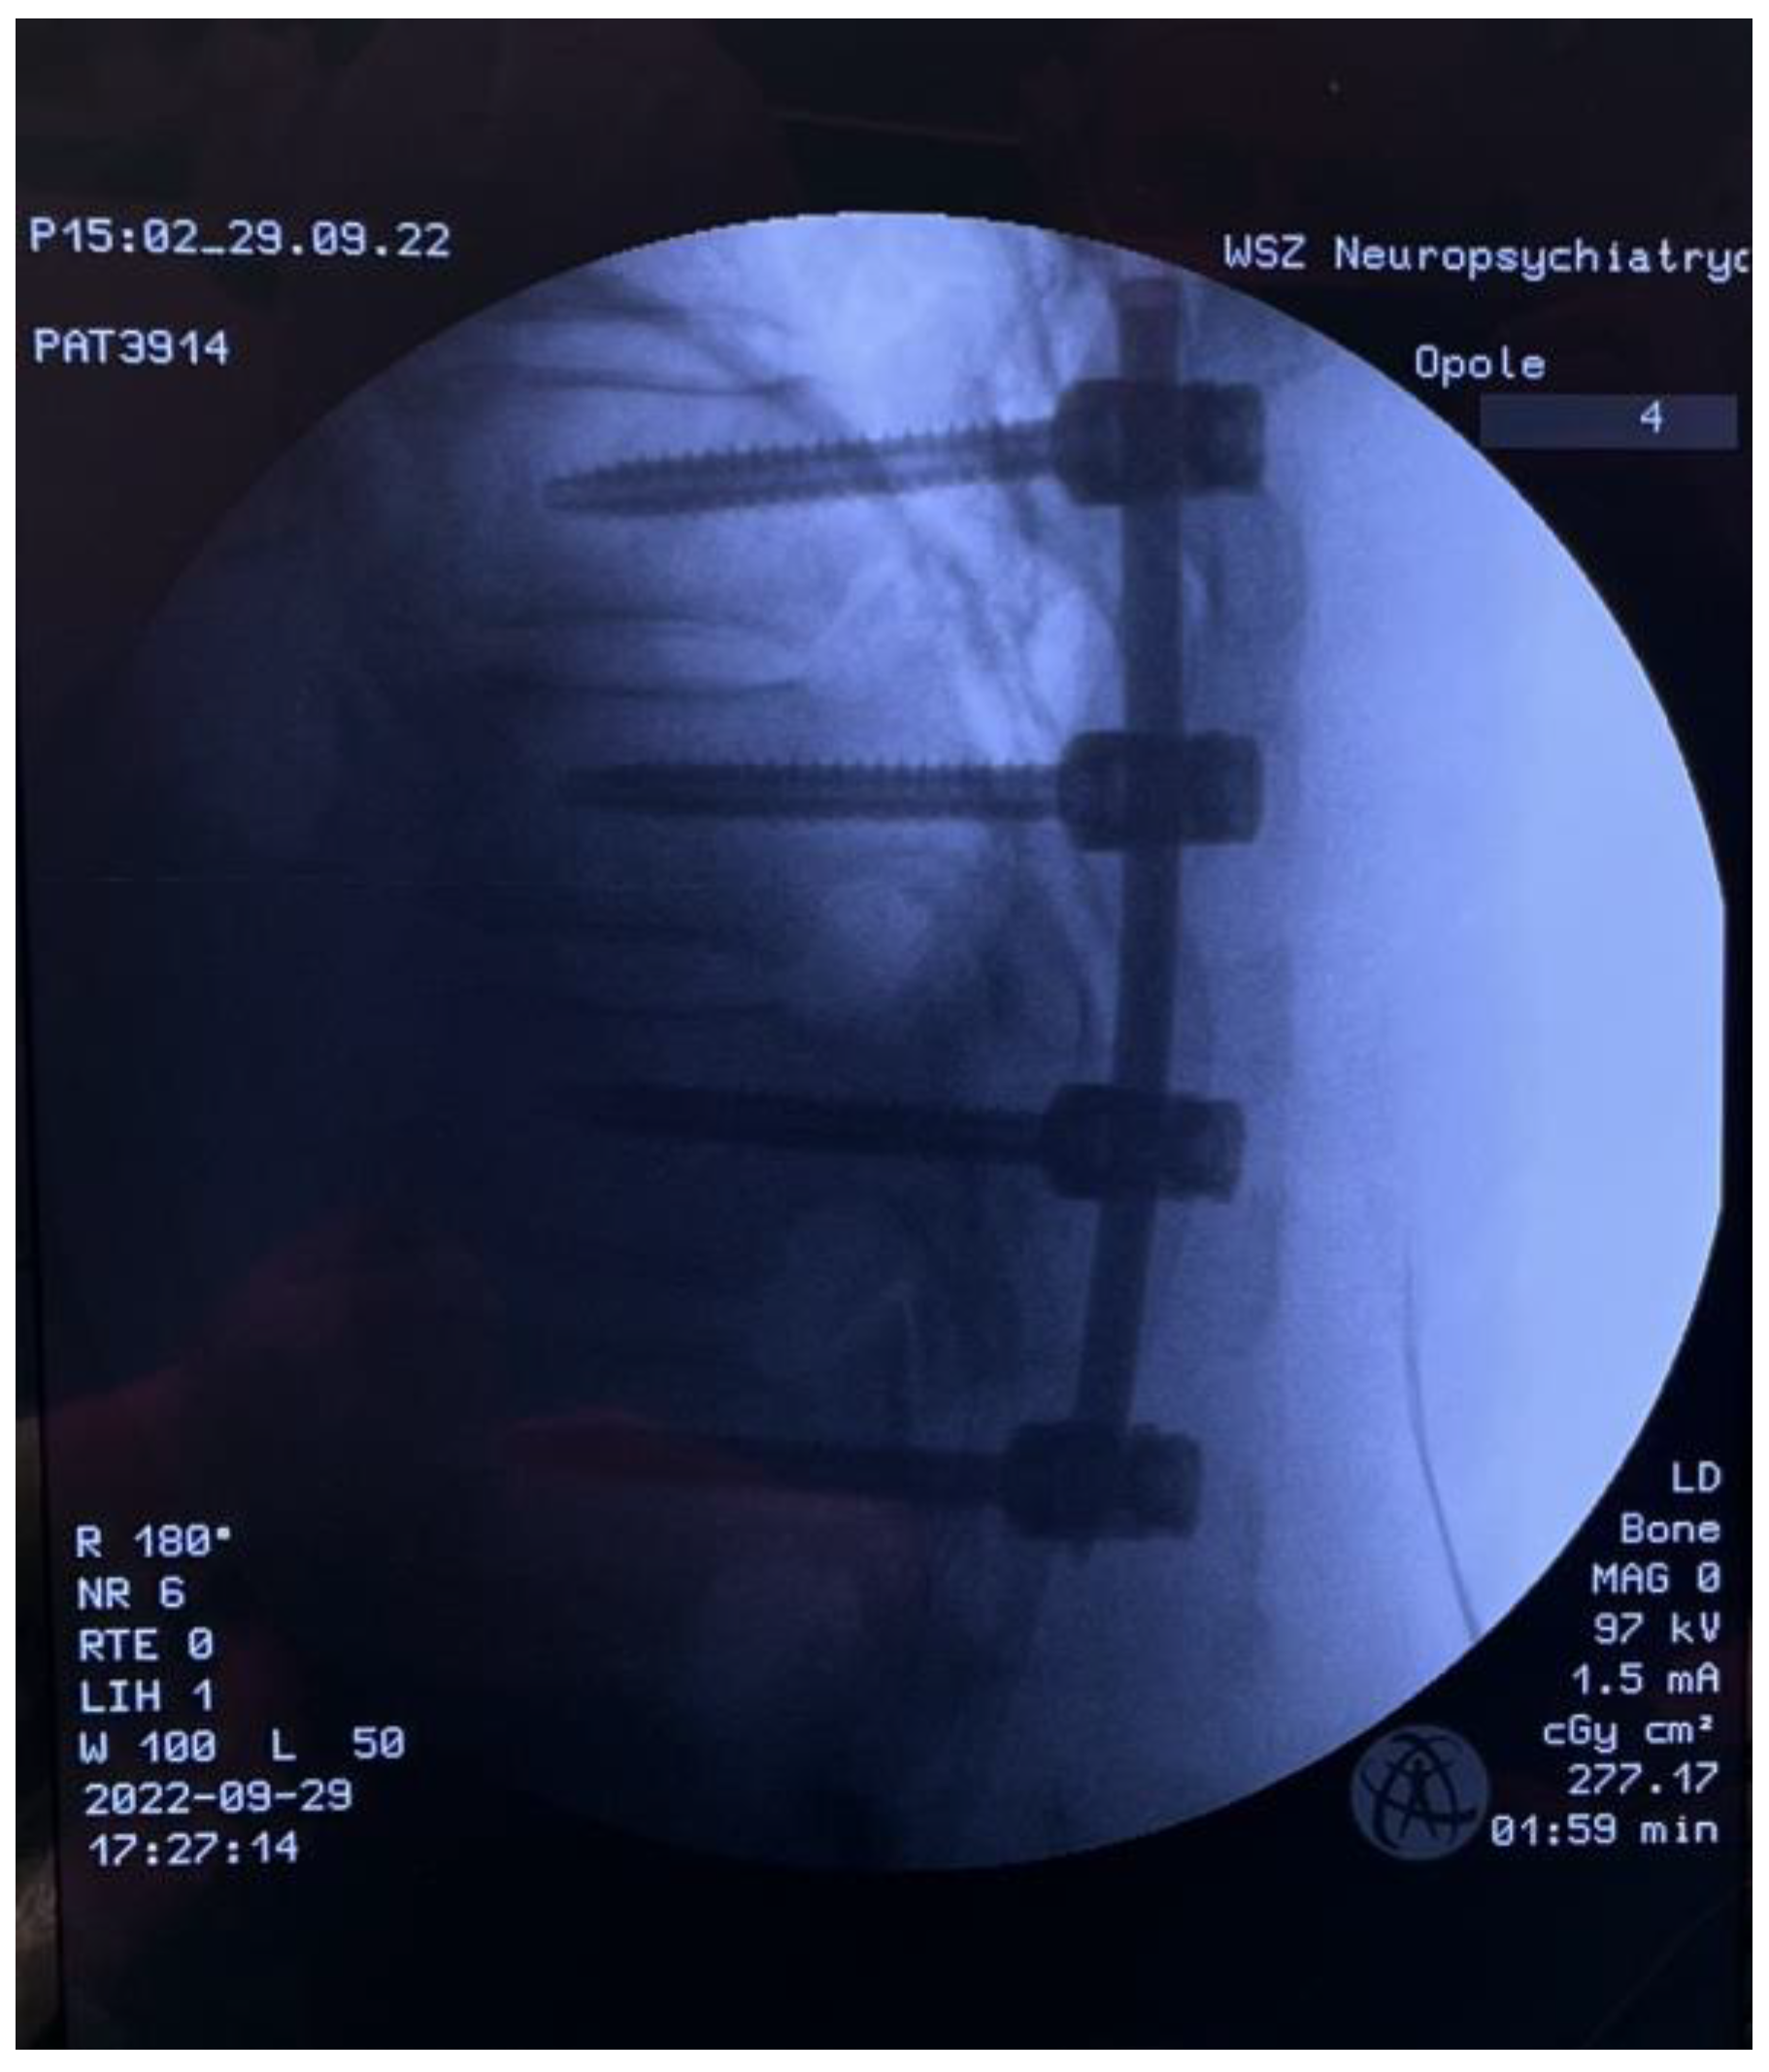

2. Materials and Methods

3. Results